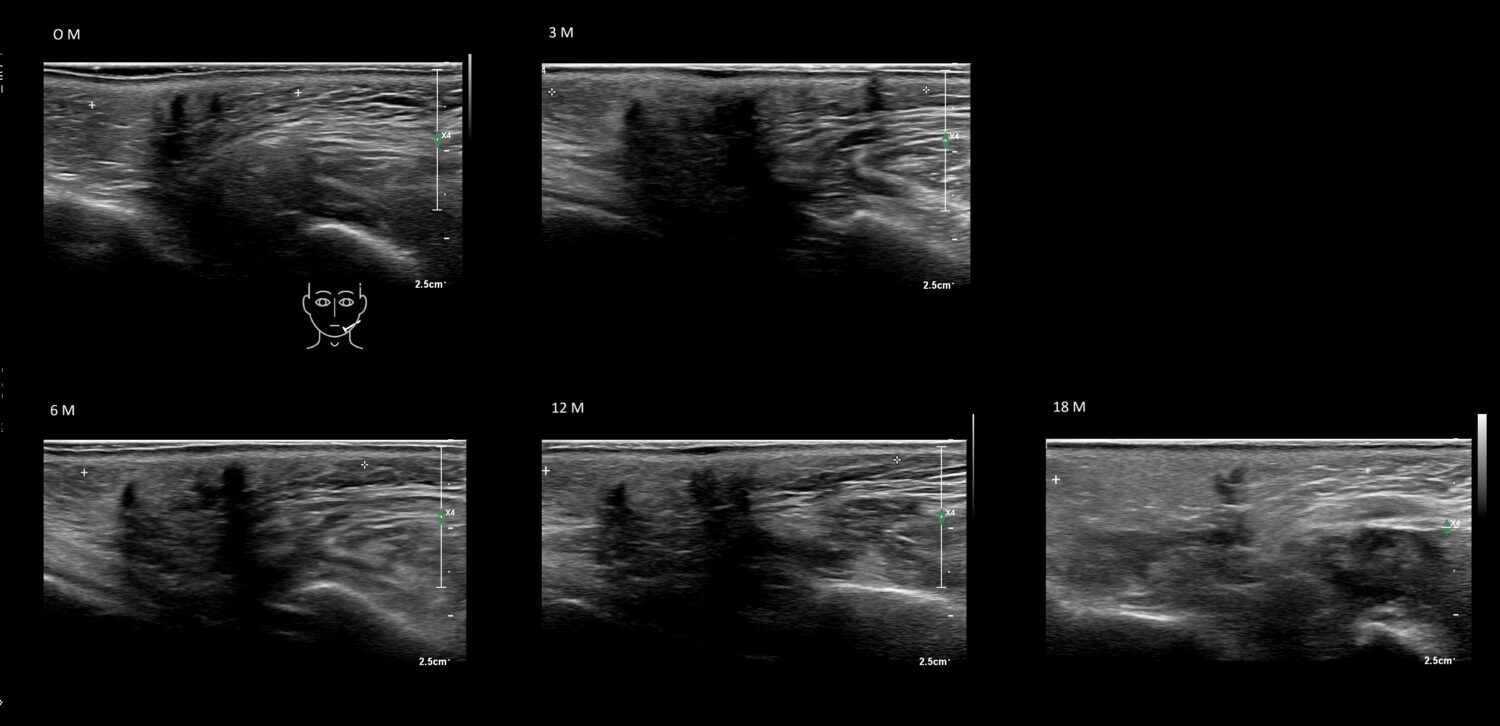

Fillers

Draw in the image on the right where the fillers are located. To check if your answer is correct, please click on the secondary image.